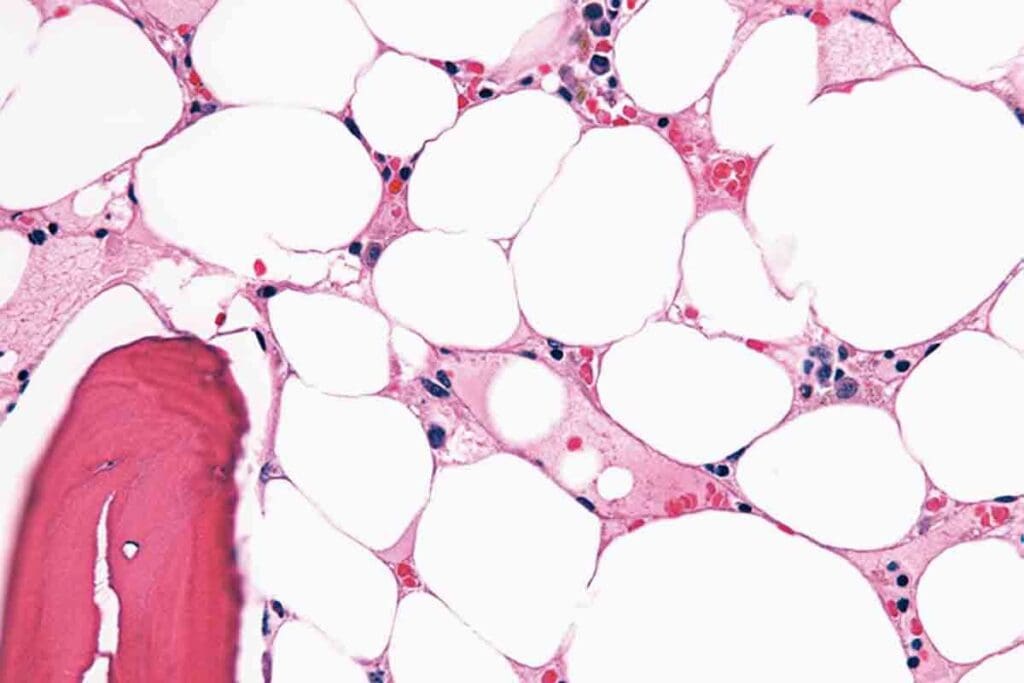

Bone Marrow Examination

A bone marrow examination is a key diagnostic tool. It involves taking a sample of bone marrow for microscopic examination.

Bone marrow findings in aplastic anemia may include:

• Aplastic or hypoplastic marrow, indicating a reduction in marrow cellularity

• Replacement of marrow with fat cells

• Absence or reduction of hematopoietic cells